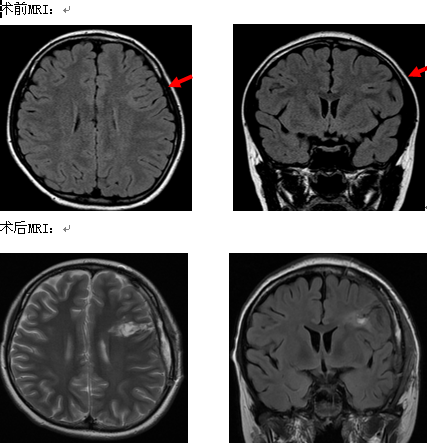

诊疗意见:①病程10月,发作表现刻板,目前药物难治性癫痫,病因考虑皮层发育不良(FCD),建议手术治疗;②致痫区考虑左侧额下沟、中央前沟,但需鉴别盖部,需要SEEG植入明确病变边界及Mapping Broca区。经SEEG证实致痫区为左侧额中央区,2016-6-15术中唤醒下给予额中央区致痫灶切除术,病理结果为:左侧额中央区符合局灶性皮层发育不良(FCD Ib),术后患者癫痫发作终止,语言功能未受损,术后至今无发作。